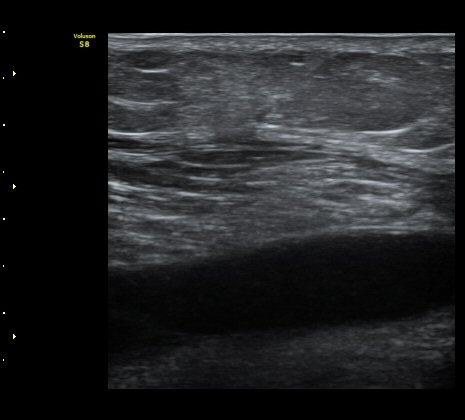

ÃÊÀ½ÆÄ À¯µµÇÏ ¼ö¾× ÈíÀÎ(÷ºÎ µ¿¿µ»ó) ÈÄ ¾Ð¹ÚºØ´ë °íÁ¤.

³»Ãø ºñº¹±Ù ÆÄ¿Àº ´ë°³ ±Þ¼ºÀ¸·Î ¹ß»ýÇÏ¿© °æÇèÀÌ ÀÖ´Â ÀÇ»ç´Â ºñº¹±ÙÆÄ¿À» ÃßÁ¤ÇÒ ¼ö ÀÖ´Ù.

±×·¯³ª °æ¹ÌÇÑ ÆÄ¿ ÈÄ ¹«¸®ÇÑ ¿îµ¿À¸·Î ÆÄ¿ÀÌ ÁøÇàµÇ´Â °æ¿ì ÅëÁõÀÌ Å©Áö ¾Ê°í º´·Âµµ ¶Ñ·ÈÇÏÁö ¾Ê¾Æ

ºñº¹±Ù ÆÄ¿À» ÃßÁ¤ÇϱⰡ ½±Áö ¾Ê´Ù. ÀÌ·± °æ¿ì¿¡´Â È®Áø¿¡ ÃÊÀ½ÆÄ°Ë»ç°¡ ÇʼöÀûÀÌ´Ù.